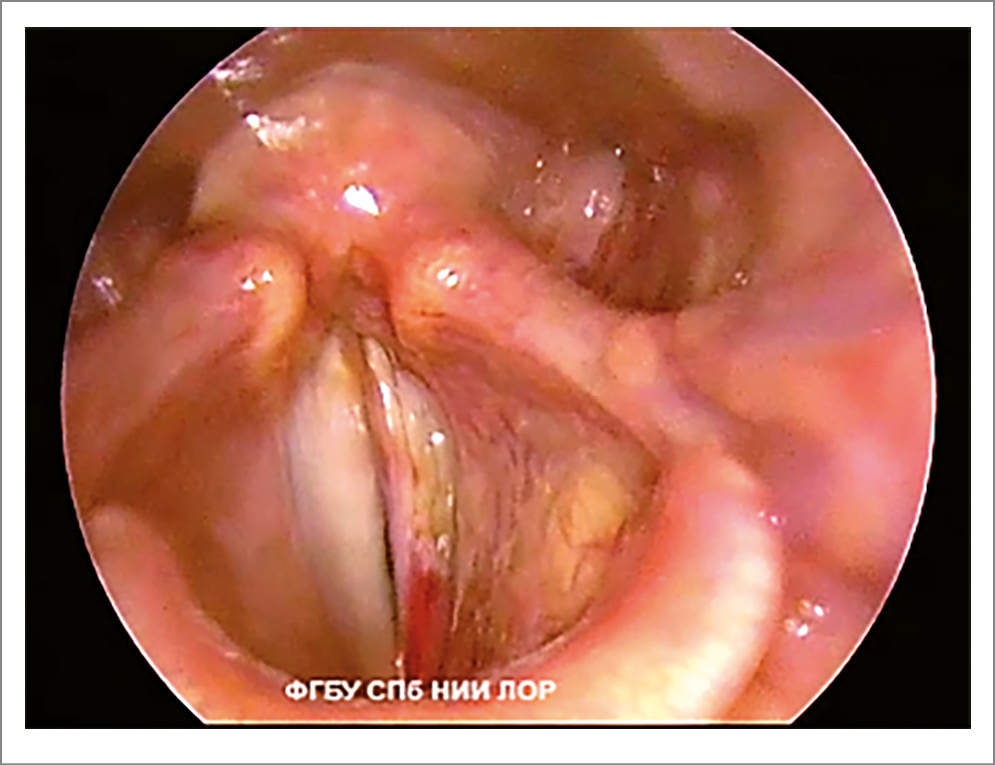

- Фонационная щель пациентов с функциональной дисфонией не соответствует форме фонационной щели здоровых людей. Изменение формы фонационной щели – основной признак гипотонуса голосовых складок. Сниженный тонус мышц гортани проявляется овальной, широкой линейной или треугольной фонационной щелью. Если у пациентов с функциональной дисфонией форма фонационной щели напоминает овал, то это свидетельствует о преимущественном снижении тонуса голосовых мышц (рис. 1). При снижении тонуса межчерпаловидных мышц фонационная щель имеет вид треугольника с верхушкой в передней комиссуре и основанием в межчерпаловидной области (рис. 2).

Рис. 2. Функциональная дисфония по гипотонусному типу (фонация): треугольная щель.